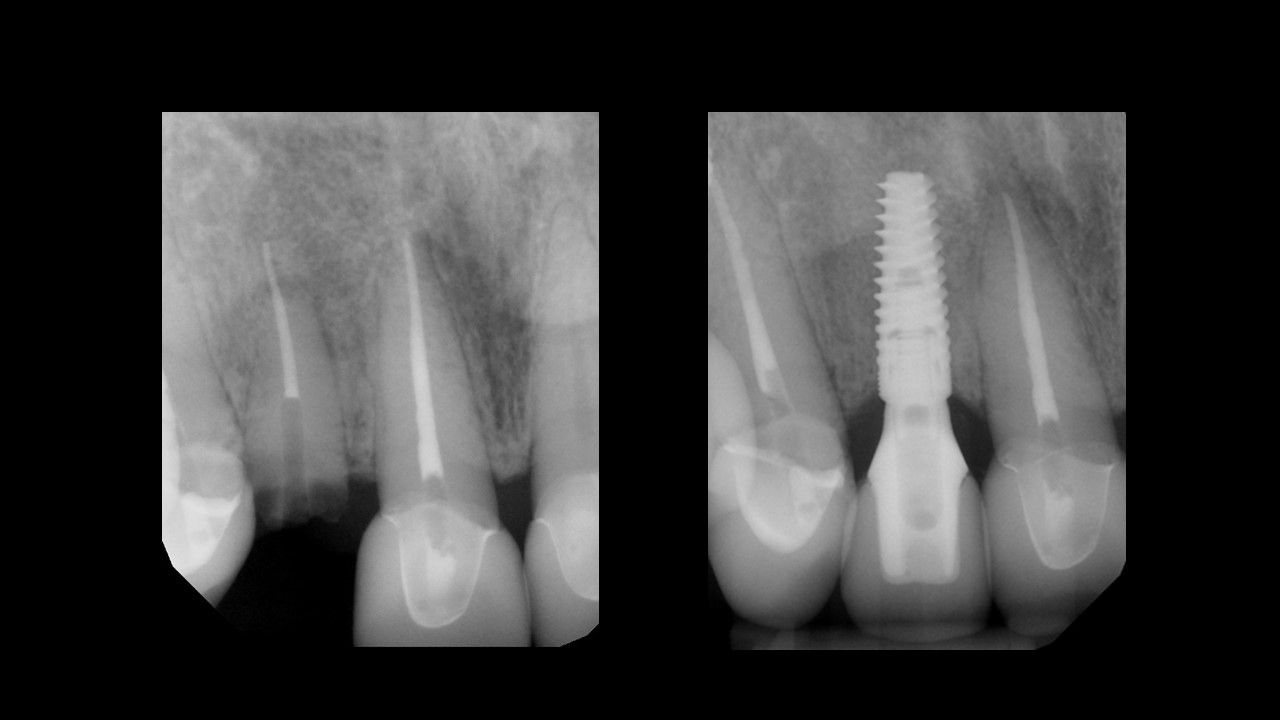

Utilising procedure-based education1, this level will help the clinician grow into more advanced surgical and prosthetic concepts with the treatment of single tooth anterior implant cases

Throughout this level, the cases will cover topics including: Evaluating buccal and apical bone for immediate placement, Grafting around immediate implants (Dual Zone Technique), Defining implant orientation – The Rules of Six, Assessing primary stability for immediate provisionalization, CAD/CAM abutment options and designs. At the completion of this level, participants will understand how to place and restore a single-tooth implant in the anterior zone. Participants are encouraged to continue their education in Level 4, which will focus on multi-unit cases.